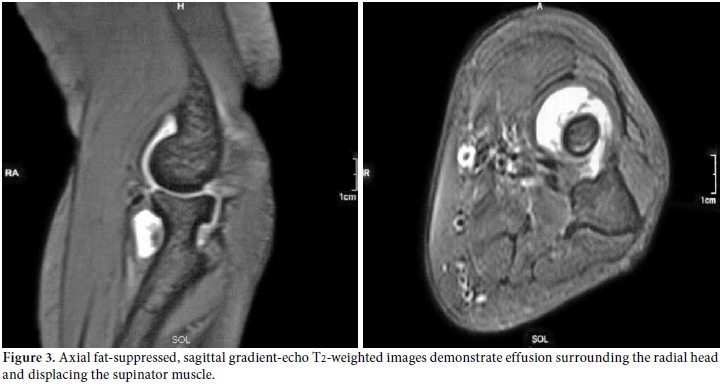

The diagnostic approach, including a careful clinical examination, non-invasive imaging techniques (US, MRI), and electrophysiological assessment were sufficient to obtain the diagnosis of PIN palsy. The patient refused to be assessed surgically, so we reconsidered and rearranged her medication by increasing the methotrexate dosage to 15 mg/week and also subcutaneously, drained the fluid and injected methylprednisolone acetate (40 mg/mL) intra-articularly by using the lateral approach to the center of the triangle formed by the lateral olecranon, the head of the radius, and the lateral epicondyle.[7] The patient was followed up via clinical, US and electrophysiological assessments every three months. Her symptoms improved the second month after the injection, and they completely resolved at the sixth month without surgical intervention. The ultrasonographic resolution was noted at the third month, but better recruitment was obtained at sixth month from the affected muscles. However, fibrillation potentials remained albeit with a smaller amplitude size. Revisualization by MRI, repeated at the 18th month, detected resolved effusion with clinical stability (Figure 4).